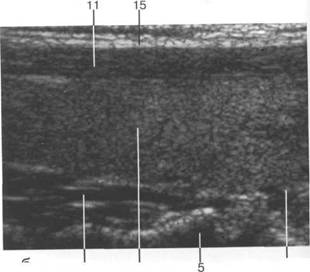

железы при поперечном сканировании.

15 28 29 |

2 28 29

2'4 5 1 25 21 |